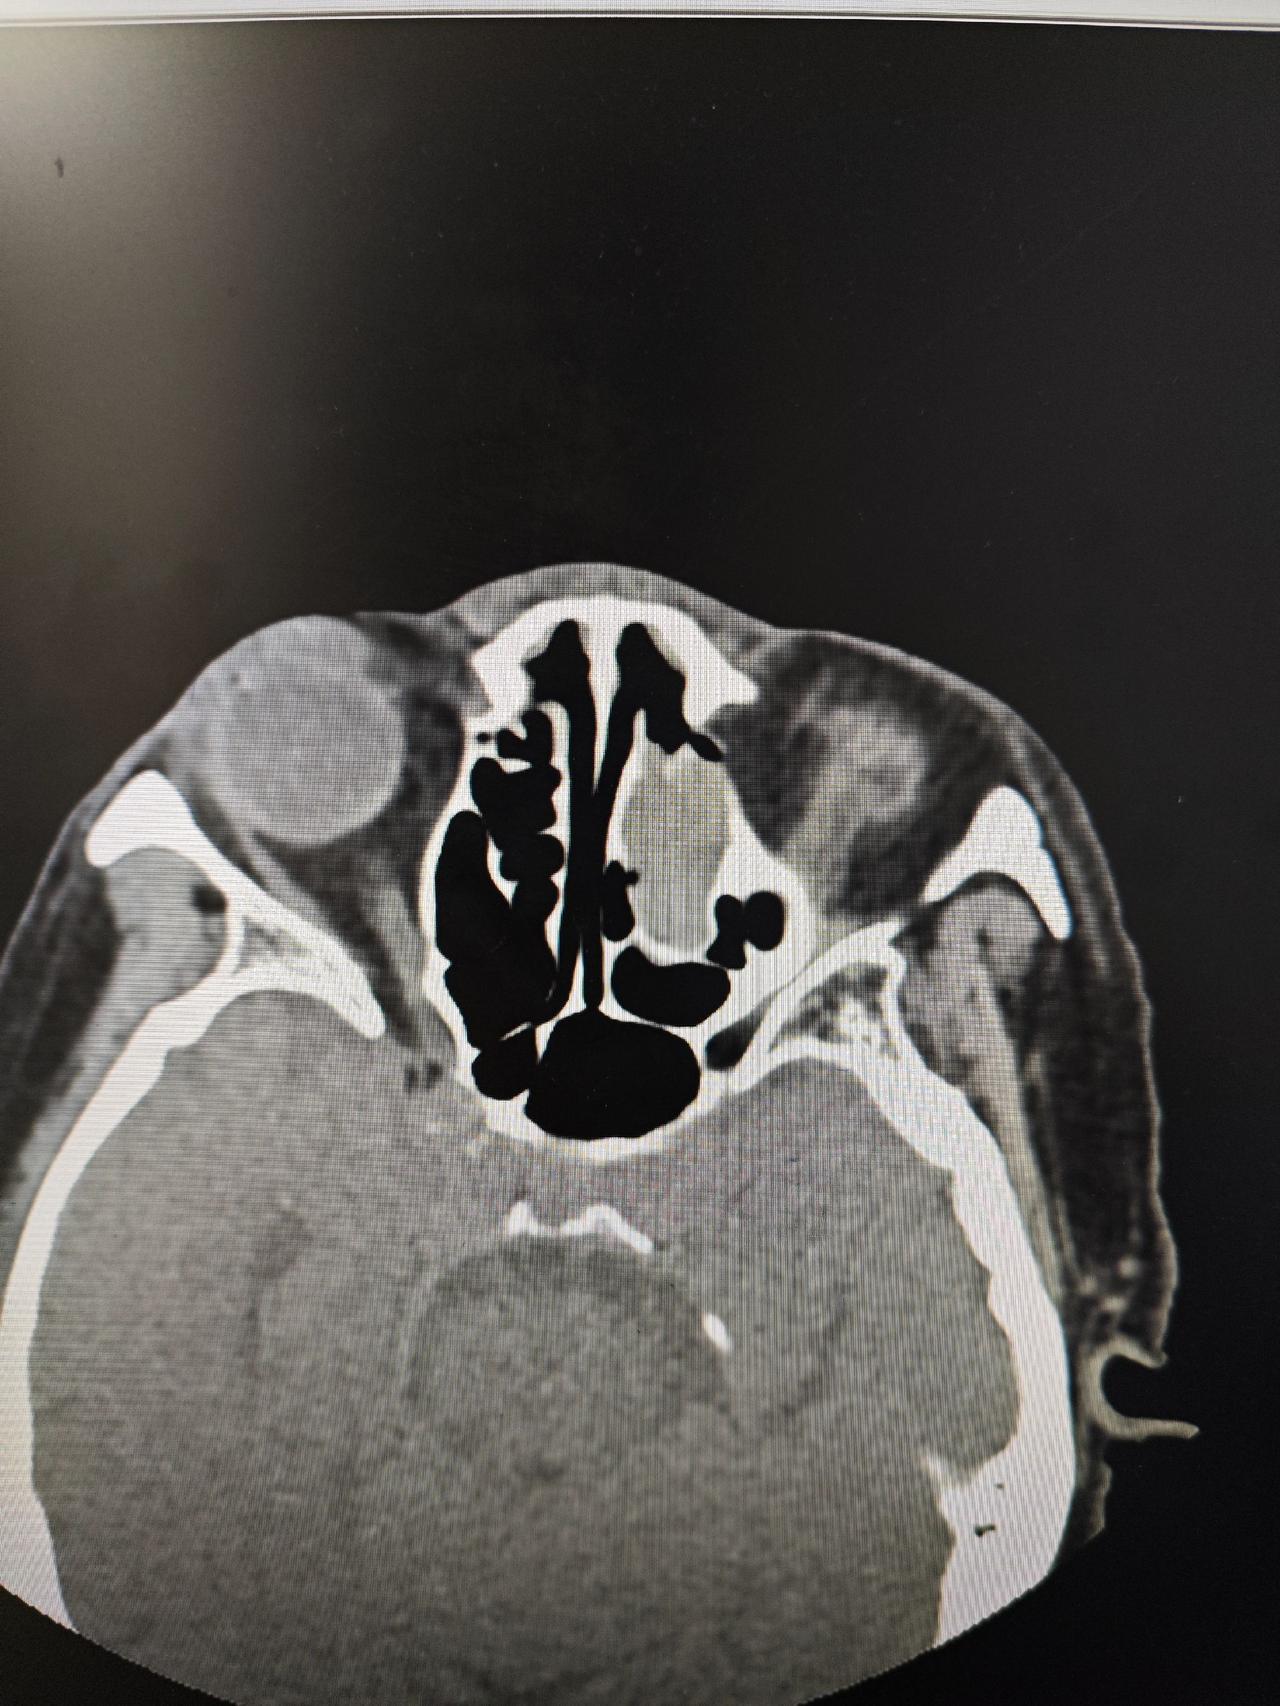

内翻性乳头状瘤,术后半年复查,预后良好

左侧鼻腔鼻窦内翻性乳头状瘤,术后三年复查,创面完全愈合,没有复发

鼻腔鼻窦内翻性乳头状瘤术后三年复查,创面完全愈合,没有复发